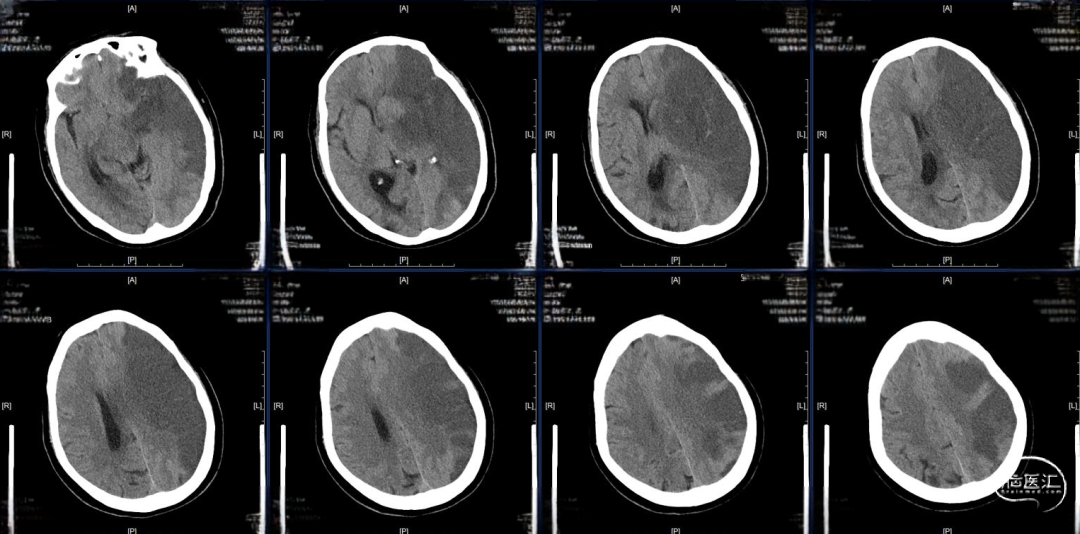

现病史:患者于2022年9月19日下午15点家务时突然出现右侧肢体无力并伴有不能言语,无发热、抽搐,当地医院急诊头颅CT提示左侧基底节区低密度病灶,未溶栓,立即送来我院,途中出现意识减退。

CT-ASPECT评分2分。

术后24小时复查CT,高灌注、轻肿胀,未见明显出血,轻度镇静至停用镇静,过程中可唤醒,自然复苏,呼吸机维持。

术后48小时复查CT,左半球大片低密度病灶、中线偏移,有主动睁眼、遵嘱动作,暂停呼吸机,延迟拔管,备去骨瓣。

术后96小时复查CT,左侧半球肿胀未继续进展,嗜睡,易唤醒、有睁眼、遵嘱动作,右侧肢体有自主动作,拔除气管插管。

术后第14天启动抗凝,术后第19天复查CT,术后第20天出院,NIHSS评分8分,mRs评分4分。